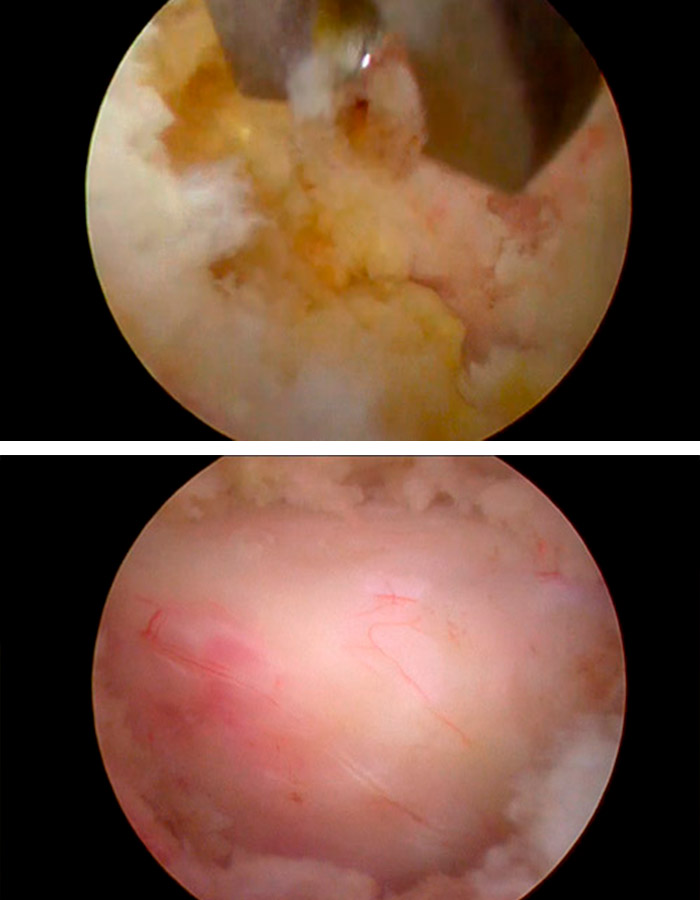

Tras la sedación, se le realiza al paciente un abordaje interlaminar posterior a través de una pequeña incisión, de apenas 3mm, en la piel mediante la que se accederá al área dónde se ubica la lesión.

Se realiza la apertura del ligamento amarillo de forma bilateral y se retira la parte hipertrofiada que comprime y cierra el canal, provocando al paciente una severa estenosis y el dolor que le impide caminar y mantenerse en pie.

Se procede a realizar una hemilaminectomía hasta comprobar la adecuada liberación de las estructuras neurológicas que recorren el canal vertebral.

Una vez comprobado que el canal tiene el espacio suficiente y que todas las partes atrofiadas han sido retiradas, se procede a retirar parte del TIP de la faceta ascendente para evitar la compresión de las estructuras neurológicas de nuevo.